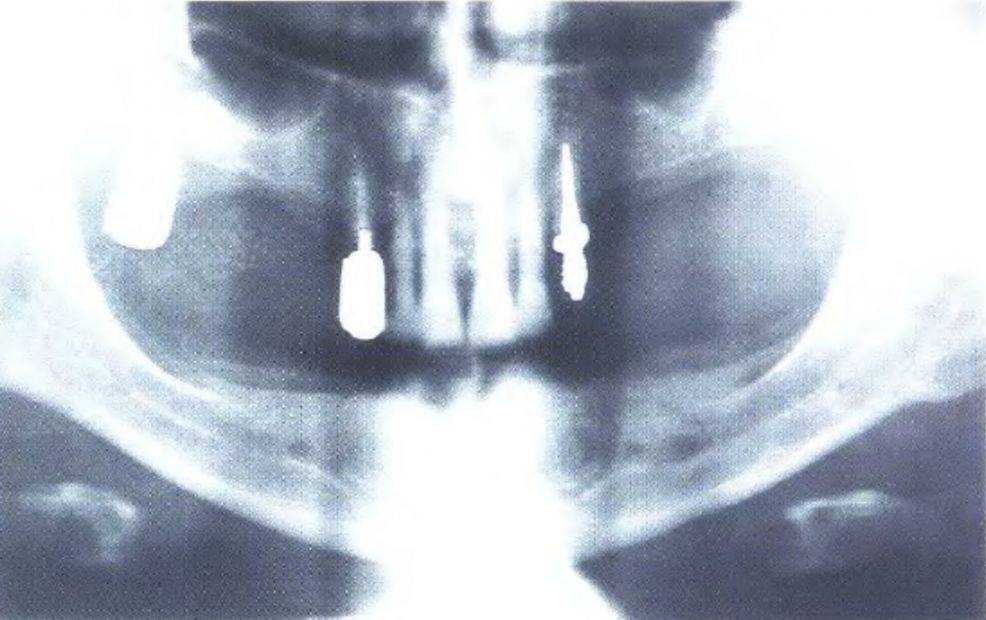

Рис. 3-39j (слева). Рентгенограмма для оценки пространства в области отсутствующего правого бокового резца

Рис. 3-39к (справа). Рентгенограмма для оценки пространства в области отсутствующего левого бокового резца

На первом этапе устранили диастему между верхними центральными резцами, чтобы создать пространство в области боковых резцов для установки имплантатов, что выполнили с помощью ортодонтического лечения (рис. с 3-39f по 3-39i). Прицельные рентгенограммы показали достаточное увеличение пространства (рис. 3-39j и 3-39к). Расстояние между верхушками корней можно было увеличить еще больше при использовании ретракционной проволочной дуги с петлями. Следует обсудить с ортодонтом варианты ортодонтического лечения. При проведении рентгенологической диагностики не следует соблюдать рекомендованный производителем оборудования протокол - необходимо подобрать параметры, которые используются при параллельном расположении зуба относительно пленки. Это позволяет полностью отобразить протрузионную и ретрузионную плоскости одновременно. Сотрудники стоматологической клиники, проводящие рентгенологическую диагностику, должны владеть этой методикой.